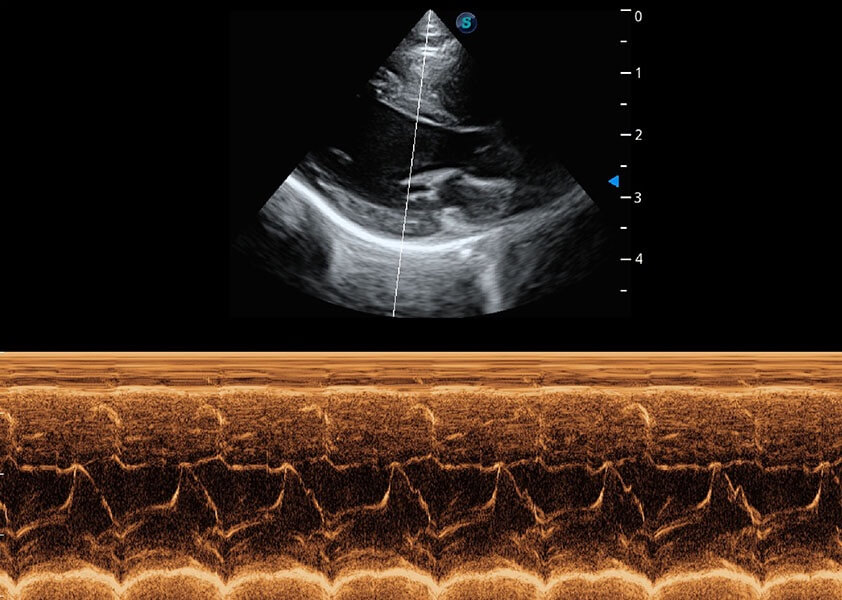

心脏解决方案

ProPet 60 配备了丰富的心脏探头群、先进的成像技术和专业的心脏测量工具,可帮助动物医生为不同体型和生理结构的动物提供心脏和心肌功能的全面评估。

• AMM 解剖M型

通过360度任意调节3条M型取样线,在同一心动周期上观察心脏不同位置的运动曲线,得到准确的心功能测量数据,有效评估心肌运动及左心室功能。

优异的基础图像

(犬)乳头肌短轴

(猫)二尖瓣M型